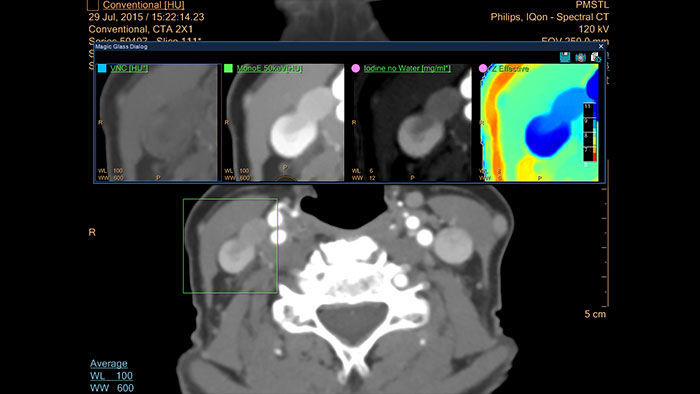

IQon Spectral CT Functionality

IQon Spectral CT is the only scanner to offer CT Spectral Light Magic Glass and CT Spectral Magic Glass on PACS, helping radiologists review and analyze multiple layers of spectral data at once, including on their PACS.

IQon Spectral CT* Functionality

The spectral viewer is optimized for analysis of spectral data sets from the IQon Spectral CT Scanner. Obtain a comprehensive overview of each patient quickly and easily, quantify quickly, and assist in diagnosis. It is designed to accommodate general spectral viewing needs with additional tools to assist in CT images analysis.

Benefits

* IQon CT reconstruction provides a single DICOM entity containing sufficient information for retrospective analysis - Spectral Base Image (SBI). SBI contains all the spectrum of spectral results with no need for additional reconstruction or post-processing. Spectral applications are creating different spectral results from SBI.